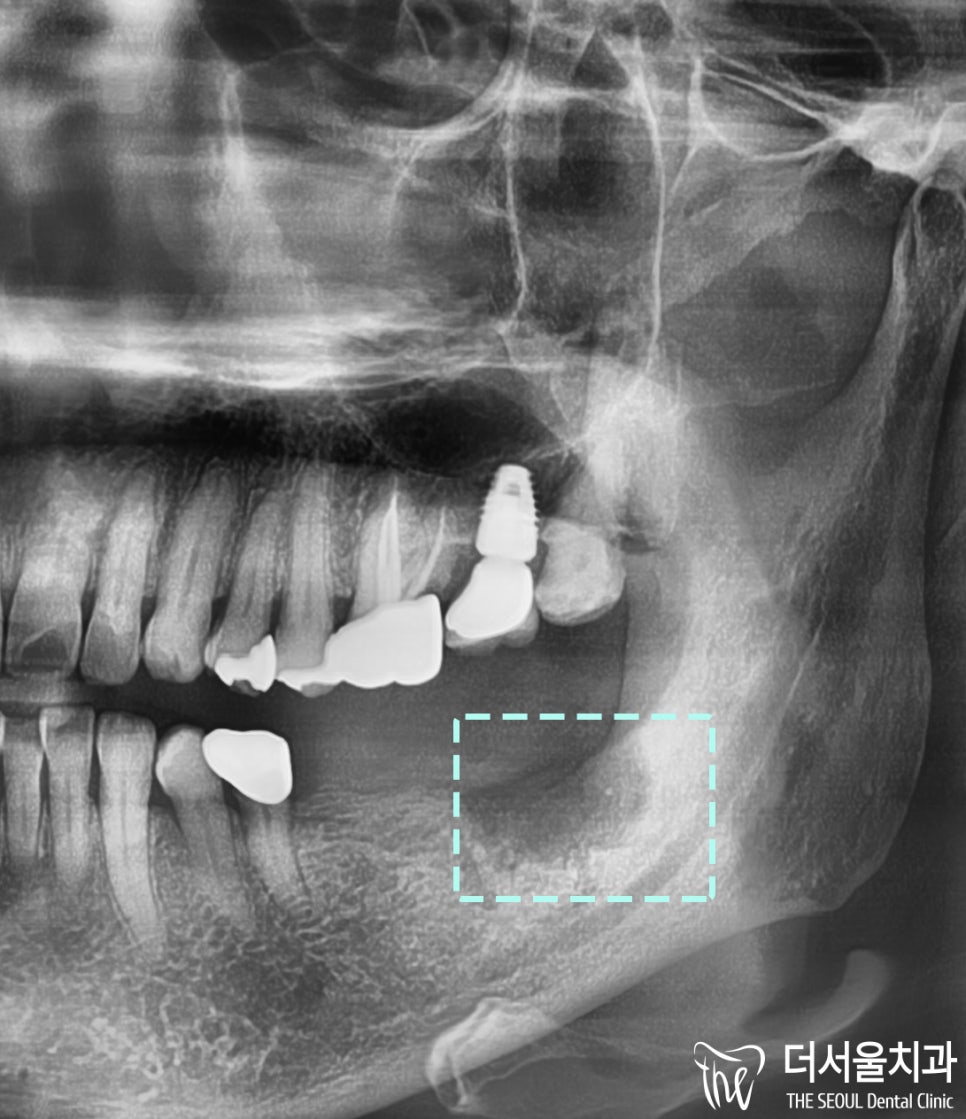

파노라마 사진을 보면

말끔하게 제거된 모습을 볼 수 있습니다 ^^

모의 수술로

픽스쳐가 심길 위치와

해부학적 구조물을 파악하고 나서

계획했던 부위에

2개의 임플란트 를 식립할 수 있었습니다.